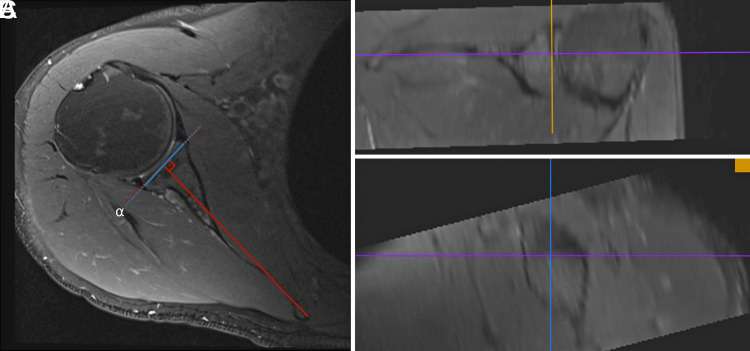

Objective: Glenoid-version-measurement methods were initially defined for computed tomography (CT) but are now used for magnetic resonance imaging (MRI). However, their accuracy and reliability on MRI have not been thoroughly investigated. The aim was to determine the accuracy of these methods on MRI and compare their reliability, hypothesizing that MRI could provide accurate measurements similar to CT using all 3 methods, with the Matsumura method having the highest reliability. Methods: Glenoid-version measurements of 40 patients (14 female, 26 males; mean age 46.5 ± 17.9 years) with glenohumeral instability were performed using the Friedman, Poon and Ting, and Matsumura methods on MRI. These measurements were compared to those on 3-dimensional corrected slices of CT scans to evaluate accuracy. Reliability was assessed by 2 observers who repeated MRI measurements after 2 months. Results: All methods demonstrated favorable accuracy. The Friedman and Matsumura methods exhibited good interobserver reliability [intraclass correlation coefficient (ICC)=0.78 (0.58-0.88) and 0.89 (0.79-0.94)], while the Poon and Ting method showed moderate reliability [ICC=0.71 (0.44-0.84)]. Intraobserver reliability was excellent for the Matsumura method [Observer 1 ICC=0.96 (0.93-0.98), Observer 2 ICC=0.86 (0.95-0.99)], good for Friedman [Observer 1 ICC=0.77 (0.57-0.88), Observer 2 ICC=0.82 (0.67-0.91)], and moderate to good for Poon and Ting [Observer 1 ICC=0.68 (0.39-0.83), Observer 2 ICC=0.82 (0.65-0.9)]. Conclusion: All 3 methods can be used confidently for MRI measurements, matching the accuracy of CT scans. The Friedman and Matsumura methods demonstrated higher interobserver and intraobserver reliabilities. Level of evidence: Level III, diagnostic study.